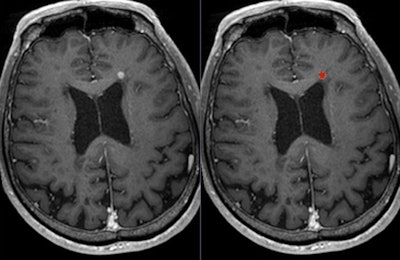

Dr. Wim Van Hecke, chief executive of Belgium-based start-up firm icometrix who will be speaking today about imaging of MS, agreed that given the recent discussions about gadolinium and its role in disease diagnosis and follow-up, it was important to evaluate its use and clinical necessity. He thinks follow-up MRI scans in MS using contrast should be questioned.

"I believe that for the diagnosis of MS, the use of a gadolinium-enhancing scan is still highly recommended. ... For the follow-up MRI scans, it should be a clinically informed decision, involving the treating clinician and the patient," he noted. "We indeed observe that the use of gadolinium for the follow-up scans is becoming less and less the rule. Instead, a gadolinium scan is requested in specific cases when its use can potentially answer a clinical question."

While, the use of contrast-enhanced MRI scans is the only way to observe blood-brain-barrier disruption due to an inflammatory lesion, Van Hecke said that recent developments of imaging analysis techniques allowed radiologists to evaluate and quantify new and enlarging T2/fluid-attenuated inversion-recovery (FLAIR) lesions, which also represent disease activity in patients with MS.